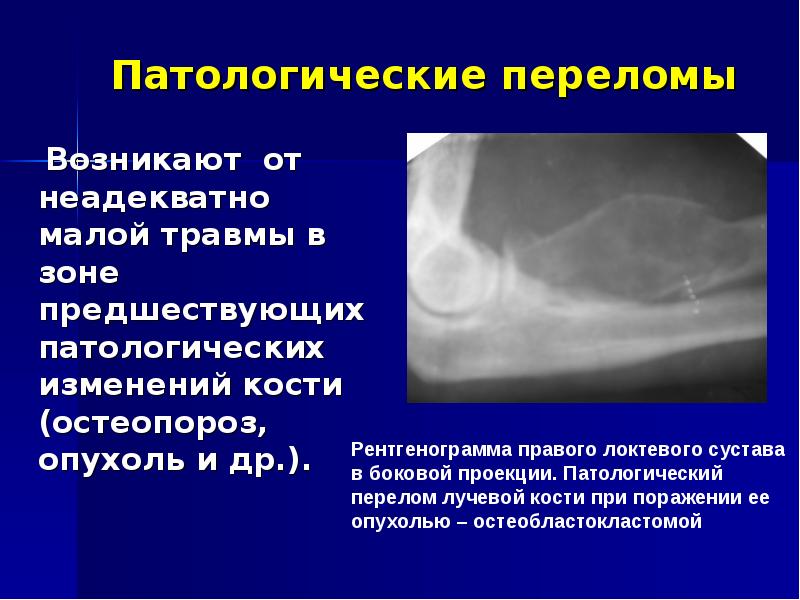

30. Патологические переломы

Возникают от

неадекватно малой

травмы в зоне

предшествующих

патологических

изменений кости

(остеопороз, опухоль

и др.).

Рентгенограмма правого локтевого сустава

в боковой проекции. Патологический

перелом лучевой кости при поражении ее

опухолью – остеобластокластомой

Патологические переломы

Возникают от неадекватно малой травмы в зоне предшествующих патологических изменений кости (остеопороз, опухоль и др.).